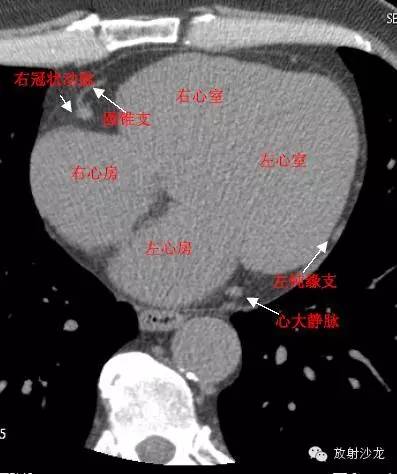

LA -Left Atrium左心房

RA -Right Atrium右心房

LV -Left Ventricle左心室

RV -Right Ventricle右心室

RCA -Right Coronary Artery 右冠状动脉

ConusBranch右动脉圆锥支

GCV–Great Cardiac Vein心大静脉